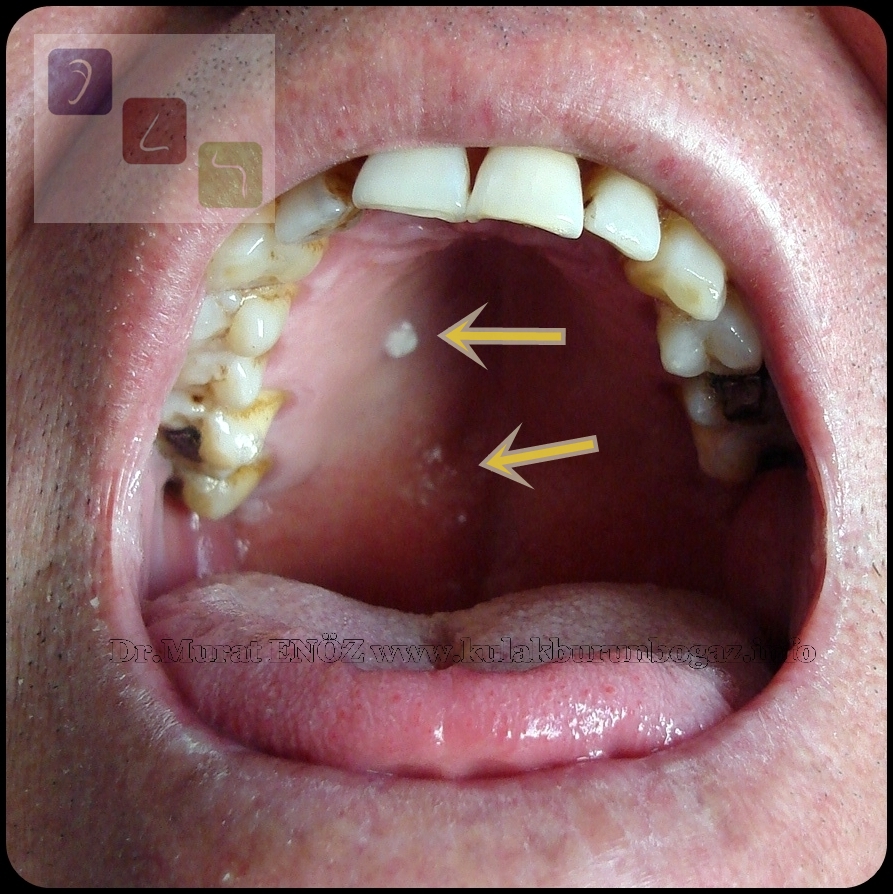

Lichen Planus Mouth

https://1.bp.blogspot.com/-j4BYG2d7f8Y/XPYWiyVZXBI/AAAAAAAA2Yo/WX-r3J01H9cN9Bshc1t1Vx2seuS7T-1-QCLcBGAs/s1600/Lichen%2BPlanus%2Bin%2BThe%2BHard%2BPalate.JPG